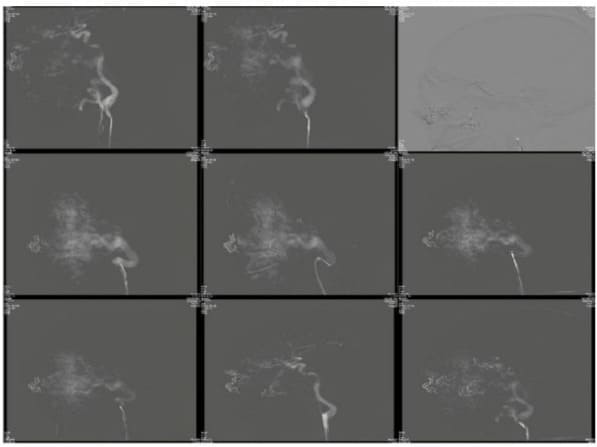

Due to the large size of the facial arteriovenous malformation and the risk of severe bleeding, the third operation opted for vascular intervention to block the blood supply vessel and perform DSA (digital subtraction angiography) first. This involved placing a catheter system with a 6F distal access catheter into the left external carotid artery trunk. A balloon catheter system was then inserted into a branch of the left external carotid artery using a guidewire. The balloon was inflated to block the blood supply artery and a total of 8 liquid embolic systems were slowly injected until it was suspected to have entered the vein. Subsequent imaging revealed a 15% decrease in blood flow to the tumor. Once the balloon is deflated, it is extracted using negative pressure retraction. Furthermore, the occlusion balloon catheter system was directed towards an alternative blood supply branch, and the blood supply artery branch was obstructed using four liquid embolization systems. Subsequent imaging revealed a decrease of around 30% in the blood flow to the tumor (Figure 4).

Figure 4: Intraoperative DSA for left-sided giant arteriovenous malformation: significant reduction in blood flow after embolization of the supplying vessels.